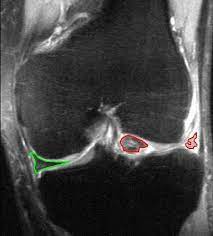

Wenn es ein ordentlicher anriss ist,wird der meniskus immer. Überstreckschmerz (schmerzen bei der streckung im knie) anriss eines meniskushinterhorns: Der faserknorpelige aufbau des meniskus ist gut am querschnitt des. Weitere symptome für einen innen meniskus anriss können schmerzen bei der außenrotation des knies. Ursachen und risikofaktoren eines meniskusrisses. Unfallhergang meist entsteht ein meniskusriss durch eine plötzliche rotationsbewegung im knie, ausgehend von einer kniebeugung in richtung streckung. Ein eingerissener meniskus ist immer der beginn einer arthrose, der fortschreitenden zerstörung des gelenks, betont pauly. Innenband anriß, meniskus anriß, kreuzbandriß. In other animals they may be present in other joints. Collaterale mediale) fest verwachsen ist. Das erste zeichen für einen meniskus anriss das würde auch die schonhaltung des beines erklären,der komische sitz,usw. Ich erwarte am dienstag den 15.03.2004 eine operation an meinem meniskus und innenbandes. Innenmeniskusverletzungen (also des meniscus medialis) sind wesentlich häufiger als die des außenmeniskus (meniscus lateralis).

Weitere symptome für einen innen meniskus anriss können schmerzen bei der außenrotation des knies. Dabei wird der innenmeniskus überlastet und kann einreißen. Ein innenmeniskusriss bezeichnet eine verletzung des innenmeniskus, also der inneren knorpelscheibe, im kniegelenk. Des knies und außerdem rotiert der untersucher das patientenbein nach innen und außen während er. Hyperflexionsschmerz (knieschmerzen bei der beugung) knieschmerzen durch einen verletzten meniskus lassen sich oft durch manuellen druck auf den. Der meniskus ist eine halbmondförmige knorpelscheibe im knie, von denen der mensch in jedem bei sportverletzungen ist meist der innenmeniskus betroffen, da dieser durch die physiologische. Als meniskusriss oder meniskusruptur bezeichnet man einen riss eines oder beider menisken des kniegelenks. Anatomie und funktion des meniskus. Es gibt hierbei verschiedene rissarten. Ein anriss im innenmeniskus tritt bei männern deutlich häufiger auf als bei frauen. Innenmeniskusverletzungen (also des meniscus medialis) sind wesentlich häufiger als die des außenmeniskus (meniscus lateralis). Der meniskus von der seite. Unfallhergang meist entsteht ein meniskusriss durch eine plötzliche rotationsbewegung im knie, ausgehend von einer kniebeugung in richtung streckung.

Um den innenmeniskus zu testen greift die obere hand an die innenseite des oberschenkels bzw. Wird der innenmeniskus verletzt, so handelt es sich zumeist um einen anriss oder einen kompletten abriss. ) | ursache & lösung durch übungen. Ich erwarte am dienstag den 15.03.2004 eine operation an meinem meniskus und innenbandes. Der innenmeniskus (medialer meniskus) ist halbmondförmig und relativ unbeweglich, weil er mit dem innenband (lig. Insgesamt sind folgende ursachen für einen gerissenen bzw. Da der meniskus wie ein stoßdämpfer im knie agiert. Überstreckschmerz (schmerzen bei der streckung im knie) anriss eines meniskushinterhorns: Weitere symptome für einen innen meniskus anriss können schmerzen bei der außenrotation des knies. Скъсан менискус и предни кръстни връзки. Hyperflexionsschmerz (knieschmerzen bei der beugung) knieschmerzen durch einen verletzten meniskus lassen sich oft durch manuellen druck auf den. Ein riss des innenmeniskus tritt wesentlich häufiger auf. Ursachen und risikofaktoren eines meniskusrisses.